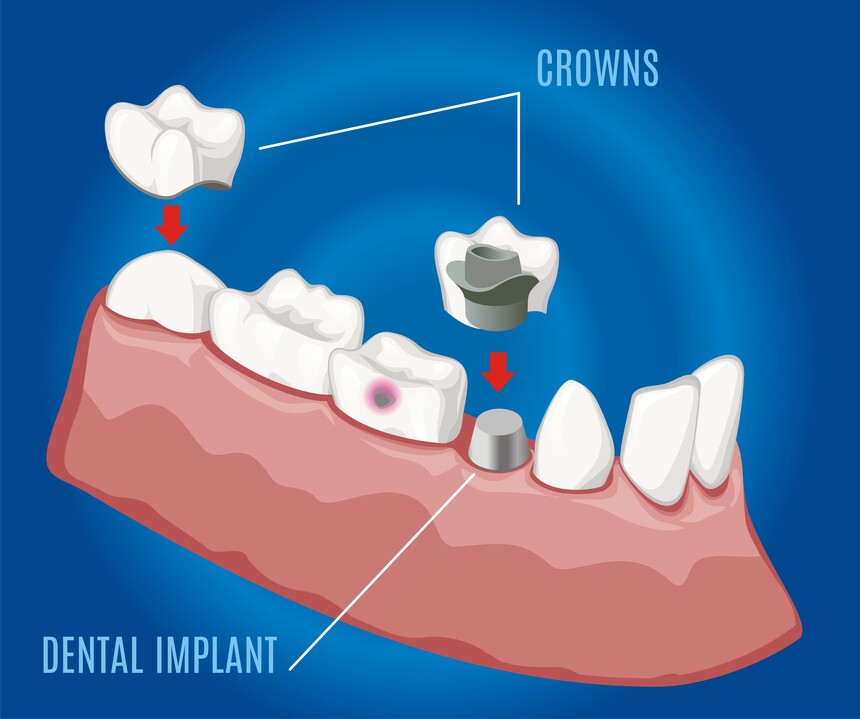

Everything You Need to Know About Dental Implants - Care32 Nashik

Dental implants have revolutionized tooth replacement, offering a durable, natural-looking soluti...

Crowns, Caps, Bridges & Dentures Clinic near College Road Nashik

Discover advanced, affordable Crowns, Caps, Bridges & Dentures Treatment near College Road Na...

Crowns, Caps, Bridges & Dentures Treatment near Gangapur Road Nashik

Looking for reliable Crowns, Caps, Bridges & Dentures Treatment near Gangapur Road Nashik<...